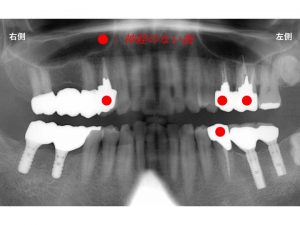

以下が

上顎がブリッジ、

下顎がインプラント治療

で対応した治療後のレントゲンです。

赤丸の歯が神経のない歯です。

まず上顎の左右のこの歯が歯根破折してしまいました。